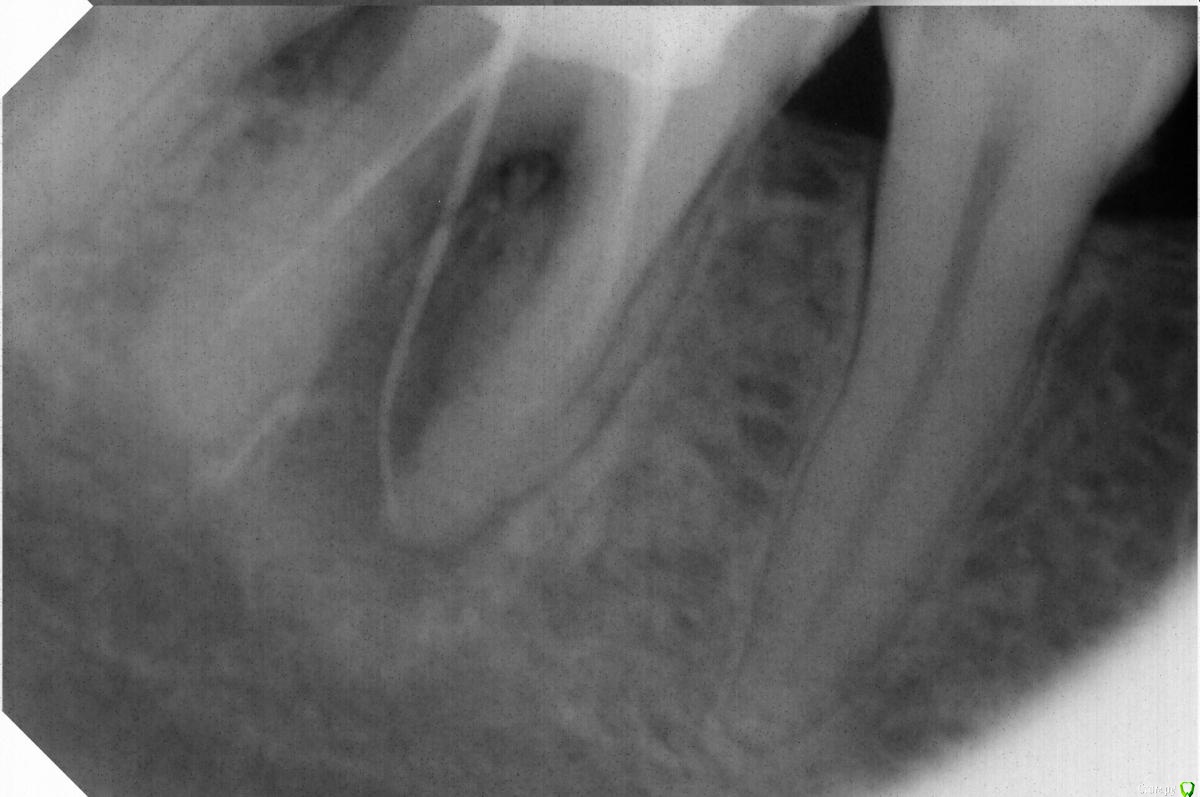

bogdan_r Опубликовано 23 июня, 2018 Поделиться Опубликовано 23 июня, 2018 Здравствуйте, у пациента жалобы на свищ, который не проходит уже 4 месяца(на момент обращения 3 месяца). Зондирование в норме. Перелечил каналы. Оставлял кальций 2 раза. Решил, что может, не достаточно плотно запломбировал и решил запломбировать гутаперчей. Вижу, что можно было сделать лучше, но свищ все равно остался. ММ канал искал, но не нашел .Может екстраканальная инфекция и нужно сделать апикальную хирургию?Какие мысли? Ссылка на комментарий

bogdan_r Опубликовано 23 июня, 2018 Автор Поделиться Опубликовано 23 июня, 2018 (изменено) Гипохлорит, лимонная кислота, ручная активация. Кофердам. Каналы розработал до 35.04. Времянка - фумка и стеклоиономер. Зондировал внимательно. Глубокого кармана, как при трещинах, не обнаружил. Изменено 23 июня, 2018 пользователем bogdan_r Ссылка на комментарий

Бендер Опубликовано 27 июня, 2018 Поделиться Опубликовано 27 июня, 2018 В апикальной части можно бы и поболя обработать Ссылка на комментарий